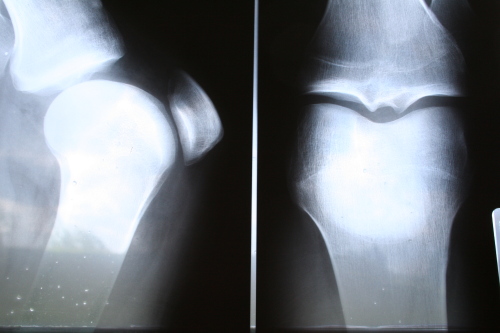

Tra le aree maggiormente colpite la spalla, il gomito, il ginocchio. Negli atleti è molto comune l’infiammazione del tendine di Achille o dei piedi, soprattutto nel tallone.